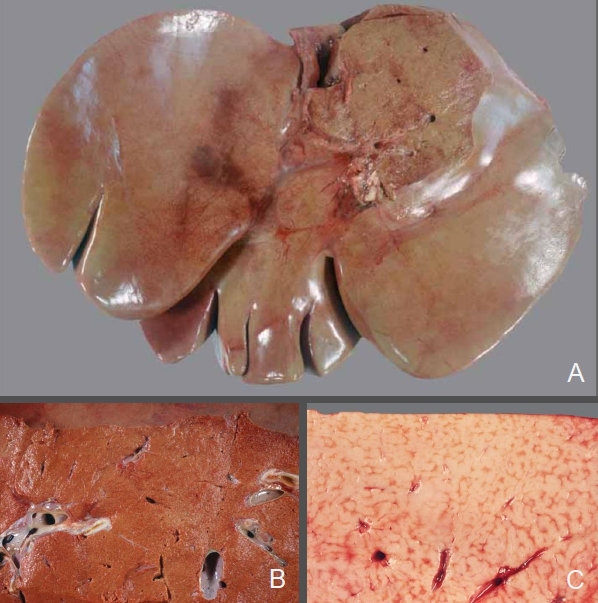

Rind, Leber: Hochgradige, diffuse Hepatolipidose

Leber

• Organ diffus verändert (A)

• Aufgehelltes Parenchym (hellbraun, gelbbraun, ocker….)

• Organ geschwollen (stumpfe Ränder, Kapsel steht unter Spannung → bei Einschnitt klaffen die Schnittränder auseinander und die Schnittflächen wölben sich vor)

• Teigige Konsistenz, Parenchym leicht eindrückbar („brüchig“)

• Fettiger Glanz der Schnittfläche (B)

• hochgradige, vermutlich panlobuläre Verfettung (C)

Hochgradige diffuse Hepatolipidose

(sog. „Fettleber“)

Hepatose (primär nicht entzündlich bedingte Stoffwechselstörung der Leber)

Pathogenese: Angebot an Fett übersteigt die Stoffwechselkapazitäten der Leber

→ Angriffspunkte der Störungen können sein: die Fettaufnahme, der Transport, verschiedene Stufen der

Verarbeitung in der Leber sowie die Ausschleusung aus der Leberzelle

Zugrundeliegende Hauptursachen:

• Alimentär/nutritiv: „Mastleber“, erhöhtes Nahrungsangebot führt zu einer vermehrten Fettspeicherung,

oftmals Begleiterscheinung einer allgemeinen Adipositas (nicht bei Sw und Pfd)

• Metabolisch: mit Hyperlipämie einhergehende Stoffwechselveränderungen → Hypoglykämie-Fettleber-

Syndrom der Zwerghunderassen, Hungerzustände (Hyperlipämiesyndrom der Ponys, Fettlebersyndrom der

Katze), Gestationshepatose bei Rd (nach Einsetzten der Laktation) und kl. Wdk (letztes Drittel der

Trächtigkeit), Diabetes mellitus beim Flfr.

• Hypoxisch: Anämie, Ischämie (z.B. durch Rückstau/verlangsamten Blutfluss im Rahmen einer

Rechtsherzinsuffizienz)

• Toxisch: z.B. Aflatoxine, Tetrachlormethan und Phosphor

DDx: Amyloidose